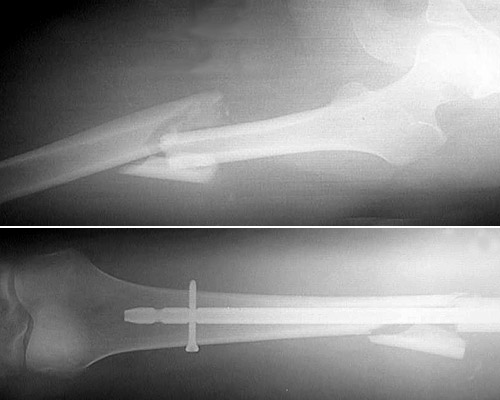

The radiograph above demonstrates a "comminuted" fracture of the femur in the upper panel, with the postoperative radiograph in the lower panel demonstrating placement of the intramedullary rod.